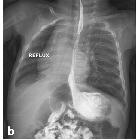

gastrooesophagealer Reflux bei Kindern

In pediatrics, the presentation is often non-specific, with vomiting, upper and lower respiratory symptoms, irritability, aversion to food, and failure to thrive . A minority of pediatric patients with GERD (<1%) will additionally have spasmodic torticollis and dystonia, a constellation of symptoms known as Sandifer syndrome .

The difficulty in the radiographic diagnosis of GERD lies in the presence of spontaneous reflux on UGI examination in 20% of normal individuals, while some patients with pathologic GERD may present with reflux only after provocative maneuvers such as Valsalva, leg raising, and coughing .

Findings associated with GERD include :

- gastroesophageal reflux (demonstrated with provocative maneuvers)